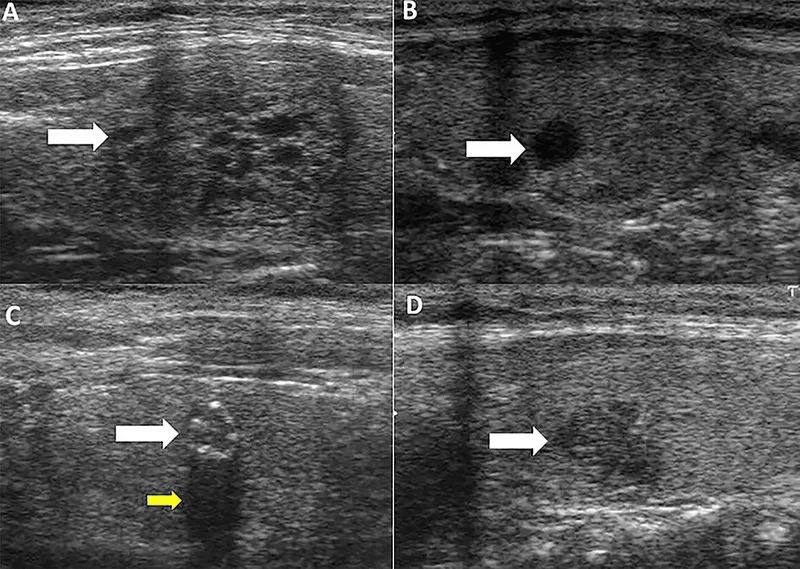

- Ultrasound (USG Neck): Initial for nodules, goiter; size, characteristics (solid/cystic), guides FNAC.